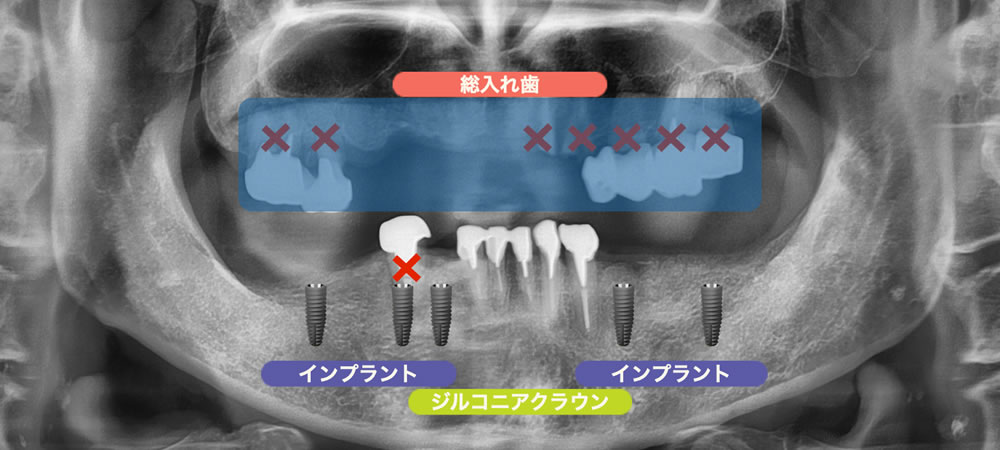

上顎は、挺出してしまい虫歯にもなっている奥歯を全て抜歯し、総入れ歯にすることで、咬合平面を整える事と見た目の改善をする事が可能になると判断しました。

下顎は、不良補綴物が入って虫歯になっている右下4を抜歯した後、前歯5本はセラミッククラウンで治療することで歯の形態を回復し、欠損部の奥歯にインプラント治療を行うことで、患者さまの要望を叶える事ができると考えました。

【治療方針】

・上顎:全て抜歯 → 自費総入れ歯

・下顎:右下4抜歯 → 前歯セラミッククラウン、奥歯インプラント